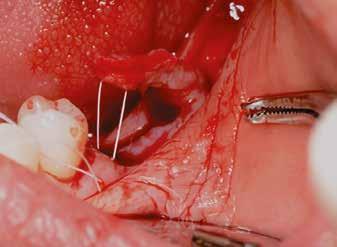

Sebészi technika

Helyi érzéstelenítést végeztünk a műtéti területen artikain és 1:100 000 adrenalin segítségével. A recipiens területet előkészítettük, élesen disszekciót végeztünk, hogy egy izomtapadástól mentes periosteum ágyat képezhessünk. Ettől disztálisan két párhuzamos parakresztális metszést végeztünk egy 15C-s szikepengével, majd a metszéseket egy

2–5. ábra: A metszések és a deepitelizáció. – 6–9. ábra: Félvastag lebeny. – 10. ábra: A nyelezett ínylebeny „bepróbálása”.

horizontális metszéssel kötöttük össze (2–5. ábra). A metszések hosszát és a köztük lévő távolságot minden esetben a lágyszövet augmentációhoz szükséges keratinizált szövet határozza meg. A lebeny deepitelizációját egy 15C-s szikepengével végeztük (6. ábra). Ezt követően félvastag lebenyt preparáltunk (7. ábra). A lebenyt apikálisan, az alapjáról belső, felületes metszéssel felszabadítottuk, hogy passzívan áthelyezhessük és rögzíthessük, feszülés nélkül. Meziális irányba 180 fokkal átforgattuk (8–9. ábra). A meziális papillát alagúttechnikával (tunnelling technique) készítettük elő a graft befogadására (10. ábra). Az így kialakított lebenyt a recipiens ágyban rögzítettük az újonnan kialakított vesztibulum alapjánál 5-0 nem felszívódó PTFE (Coreflon, IMPLACORE) varratokkal. A graftot behajtottuk az ínyszél alá és meziális oldalon rögzítettük PTFE varratokkal (11–14. ábra) A műtétet követően napi kétszeri, 0,12%-os klórhexidin tartalmú szájvízzel történő öblögetést javasoltunk a páciensnek, két héten keresztül. Gyulladáscsökkentésre 8 óránként 400 mg Ibuprofént javasoltunk, három napon keresztül. A páciens elmondása szerint sem fájdalmat, sem különösebb diszkomfortot nem tapasztalt. Ezt követően, további 4 héten keresztül, 0,2%-os klórhexidin tartalmú szájvízzel történő öblögetést javasoltunk a betegnek és instruáltuk, hogy lehetőleg ne mossa fogkefével az érintett területet. A varratokat egy héttel később távolítottuk el. A donor és a recipiens terület – 10 nappal a műtétet követően – kiválóan gyógyult (15–16. ábra). Az ezt követő kontrollokat a következő időpontokban ejtettük meg: kettő, illetve négy héttel a műtét után, majd három, hat és tizenkét hónappal később, ezt követően pedig félévente (17–20. ábra). Minden kontroll alkalmával professzionális fenntartó kezelést végeztünk a területen.